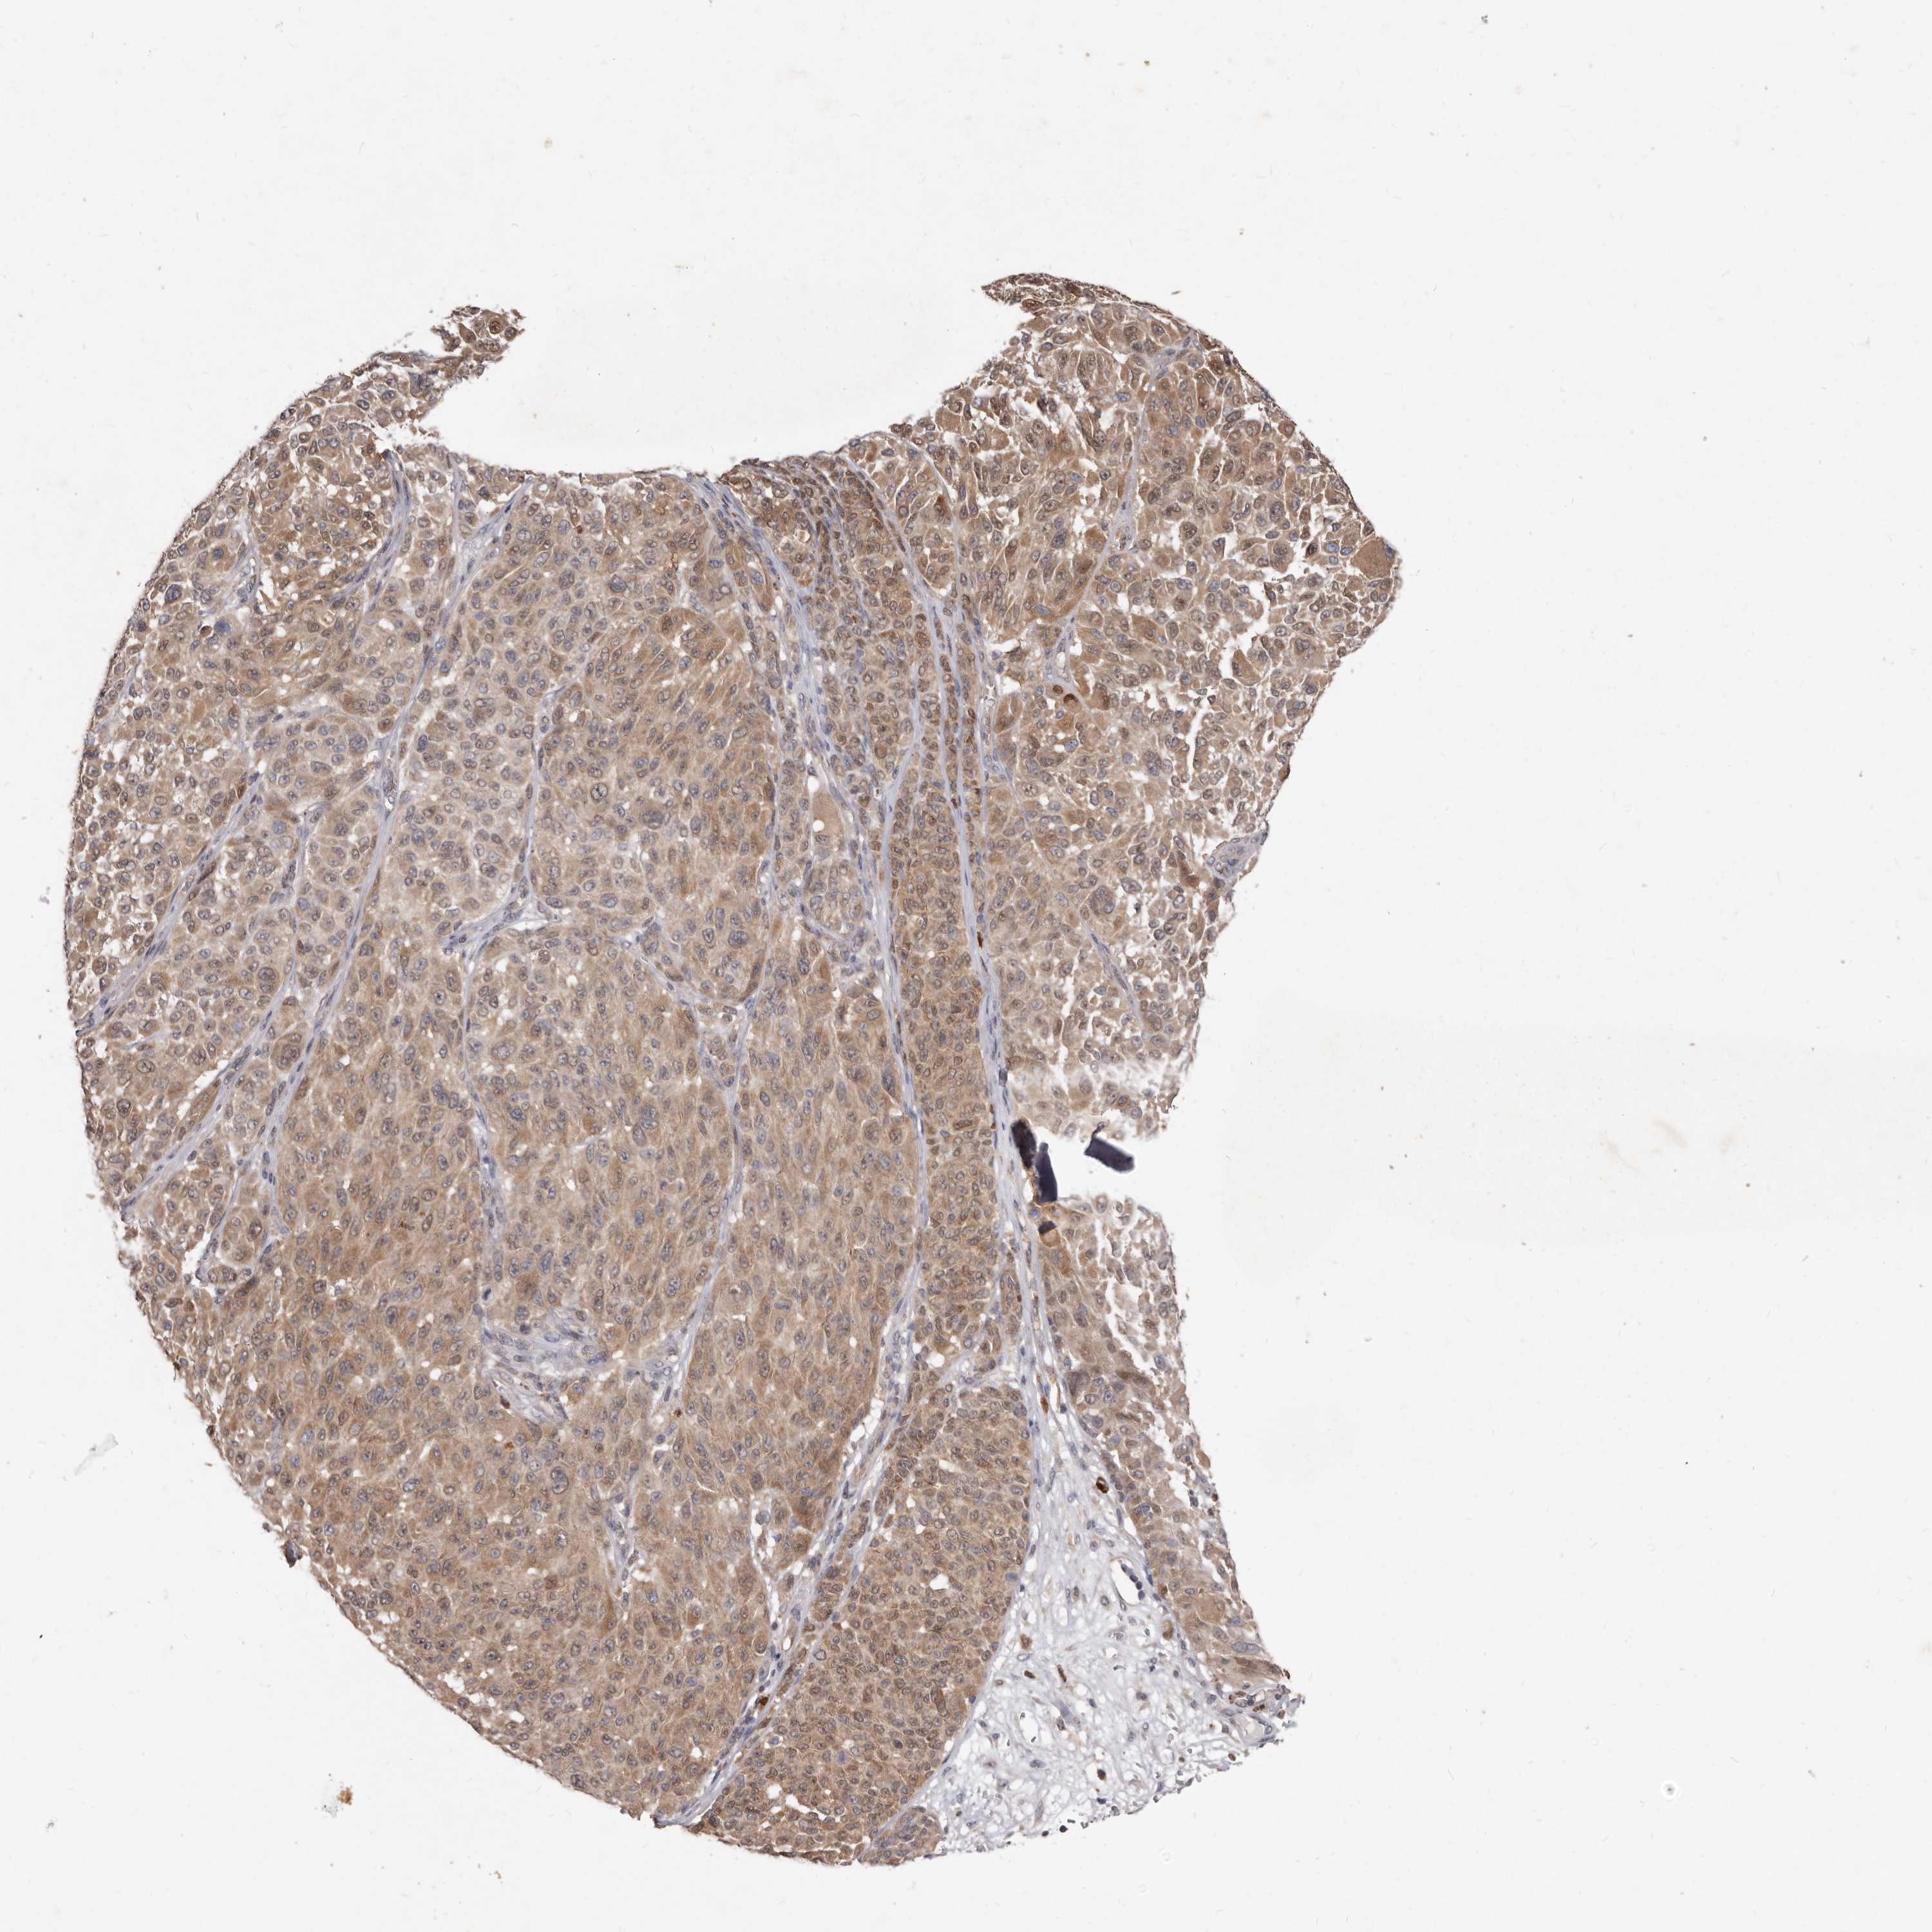

MELANOMA - Protein expressioni

A mouse-over function shows sample information and annotation data. Click on an image to view it in a full screen mode. Samples can be filtered based on level of antibody staining by selecting one or several of the following categories: high, medium, low and not detected. The assay and annotation is described here.

Note that samples used for immunohistochemistry by the Human Protein Atlas do not correspond to samples in the TCGA dataset.

Antibody stainingi

Antibody staining in the annotated cell types in the current human tissue is reported as not detected, low, medium, or high, based on conventional immunohistochemistry profiling in selected tissues. This score is based on the combination of the staining intensity and fraction of stained cells.

Each image is clickable and will lead to virtual microscopy that enables deeper exploration of all samples and also displays staining intensity scores, fraction scores and subcellular localization as well as patient and tissue information for each sample.

HPA022434

HPA022953

HPA022959

HPA028758

CAB007783

Malignant melanoma, NOS

Malignant melanoma, Metastatic site